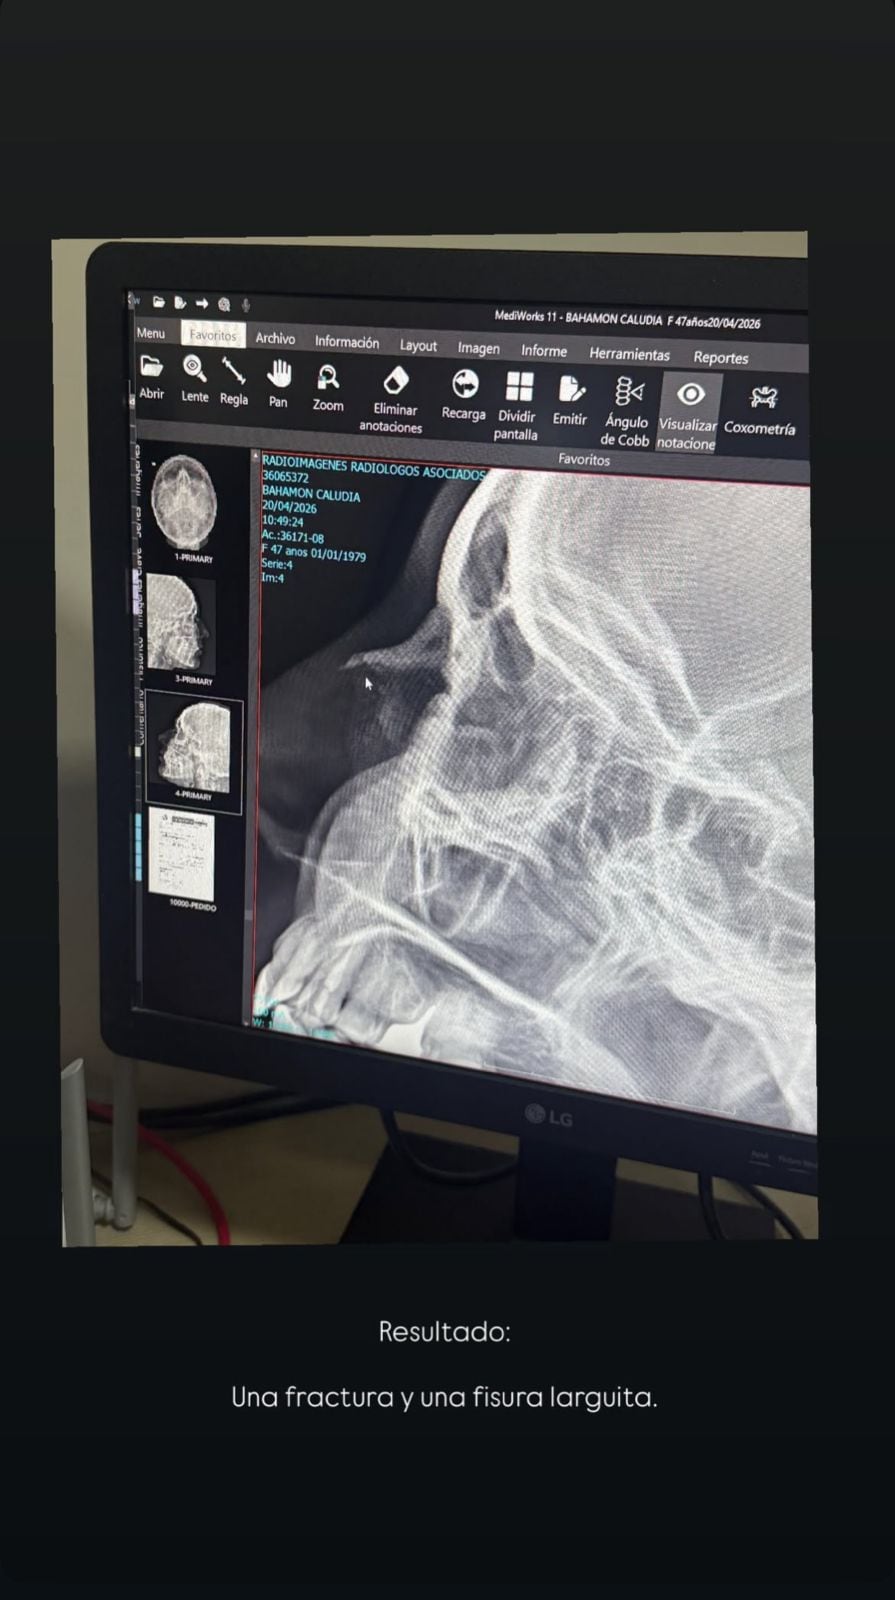

El resultado de esto fue una fractura y una fisura larga, según comentó en una RX (rayos X).